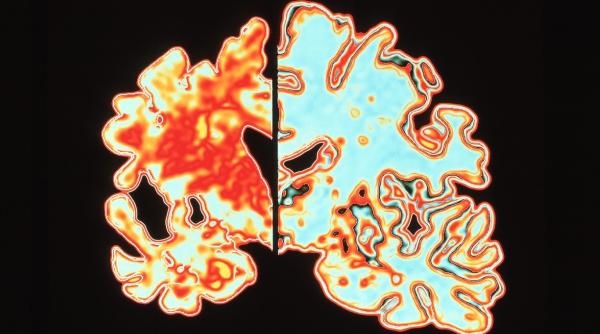

Medicamentul atacă aşa-numitele plăci amiloide, care se găsesc în creierul pacienţilor cu Alzheimer. Aceste plăci se depun între celulele nervoase din cortexul cerebral şi întrerup conexiunile dintre neuroni.